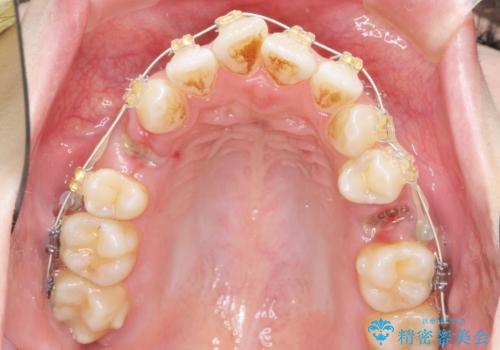

ガタつきと口元の改善 抜歯を伴うワイヤー矯正

- 唇の閉じづらさと、前歯のがたつきの改善を希望され来院されました。

抜歯を行わなくてもなんとか並べられる歯並びですが、唇の閉じづらさをしっかりと改善するため抜歯を伴うマルチブラケット矯正を行うこととしました。

前歯をしっかりと後方に引いたことで、唇は閉じやすくなり、仕上がりに満足いただくことができました。